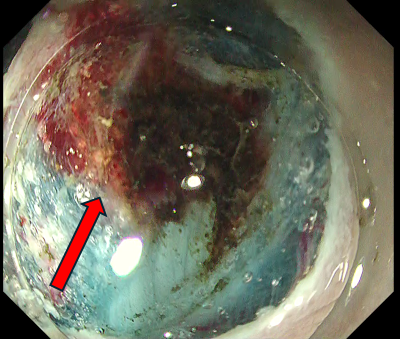

Fig. 2 shows the initial phases of case 1, illustrating how a properly executed local injection allows wide spreading with a single incision and facilitates subsequent introduction into the submucosal layer.

Fig. 1 Ideal local injection

Fig. 2